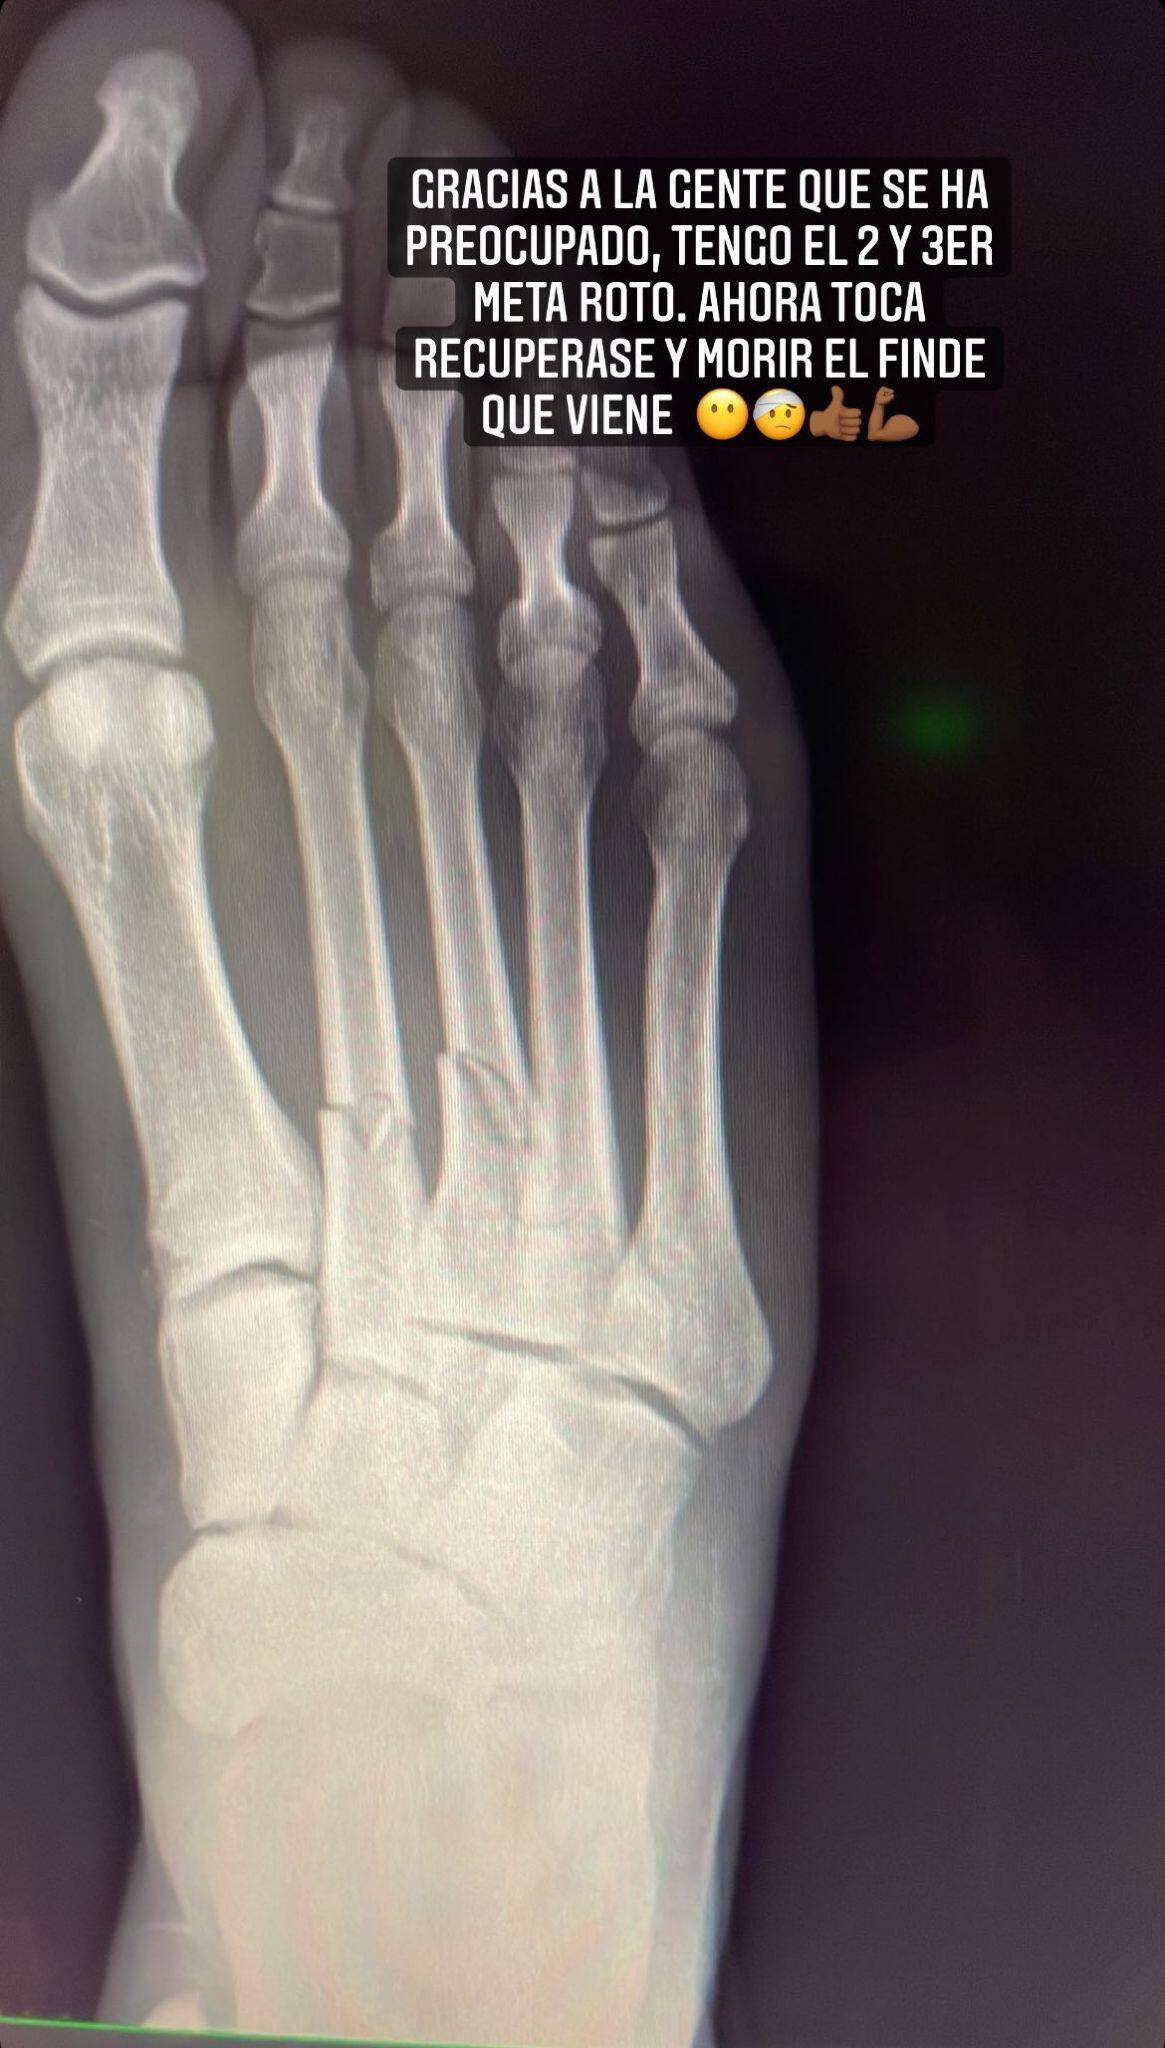

Il centrocampista del Cadice ha denunciato su Instagram lo stato del suo piede destro dopo il fallo subito da Hazard nel corso della partita di Liga con il Real Madrid. A una prima foto eloquente è stata aggiunta la radiografia che evidenzia una doppia frattura. Ma il belga se l'è cavata con un cartellino giallo

"Ringrazio le persone che si sono preoccupate per me, ho il secondo e il terzo metatarso rotti". Carlos Akapo, centrocampista della Guinea Equatoriale costretto ad abbandonare il campo al 76' di Cadice-Real Madrid, penultimo turno di Liga, ha dato un aggiornamento sul proprio piede destro via Instagram. Il contrasto con Eden Hazard, entrato leggermente a gamba tesa ma alla ricerca del pallone e senza intenzione di fare male all'avversario (tanto che poi è stato solo ammonito) gli è costata un finale di stagione che si preannuncia da cardiopalma per i tifosi del Cadice, in piena lotta salvezza. Al termine della sfida con il Real, terminata 1-1, Akapo aveva pubblicato una foto del piede ferito. Qualche ora dopo il vedetto con tanto di radiografia pubblicata nelle stories di Instagram: doppia frattura, la sfida di domenica in casa dell'Alaves non potrà vederlo protagonista in campo.